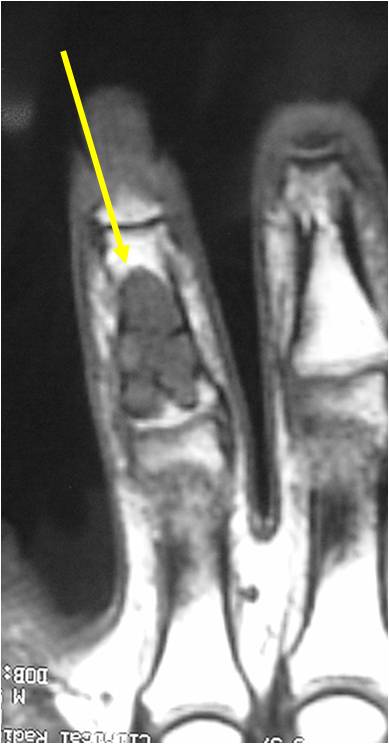

- MRI

- Lobulated margin

- Marked increased intensity long TR images

- Calcified chondroid – low intensity all sequences

MRI:

- Lobulated margin (Lobular Growth Pattern)

- T1 Weighted Images: Intermediate Signal Intensity

- Calcifications will be low signal

- T2 Weighted Images: High Signal Intensity

- High water content shows as high signal on T2 weighted images